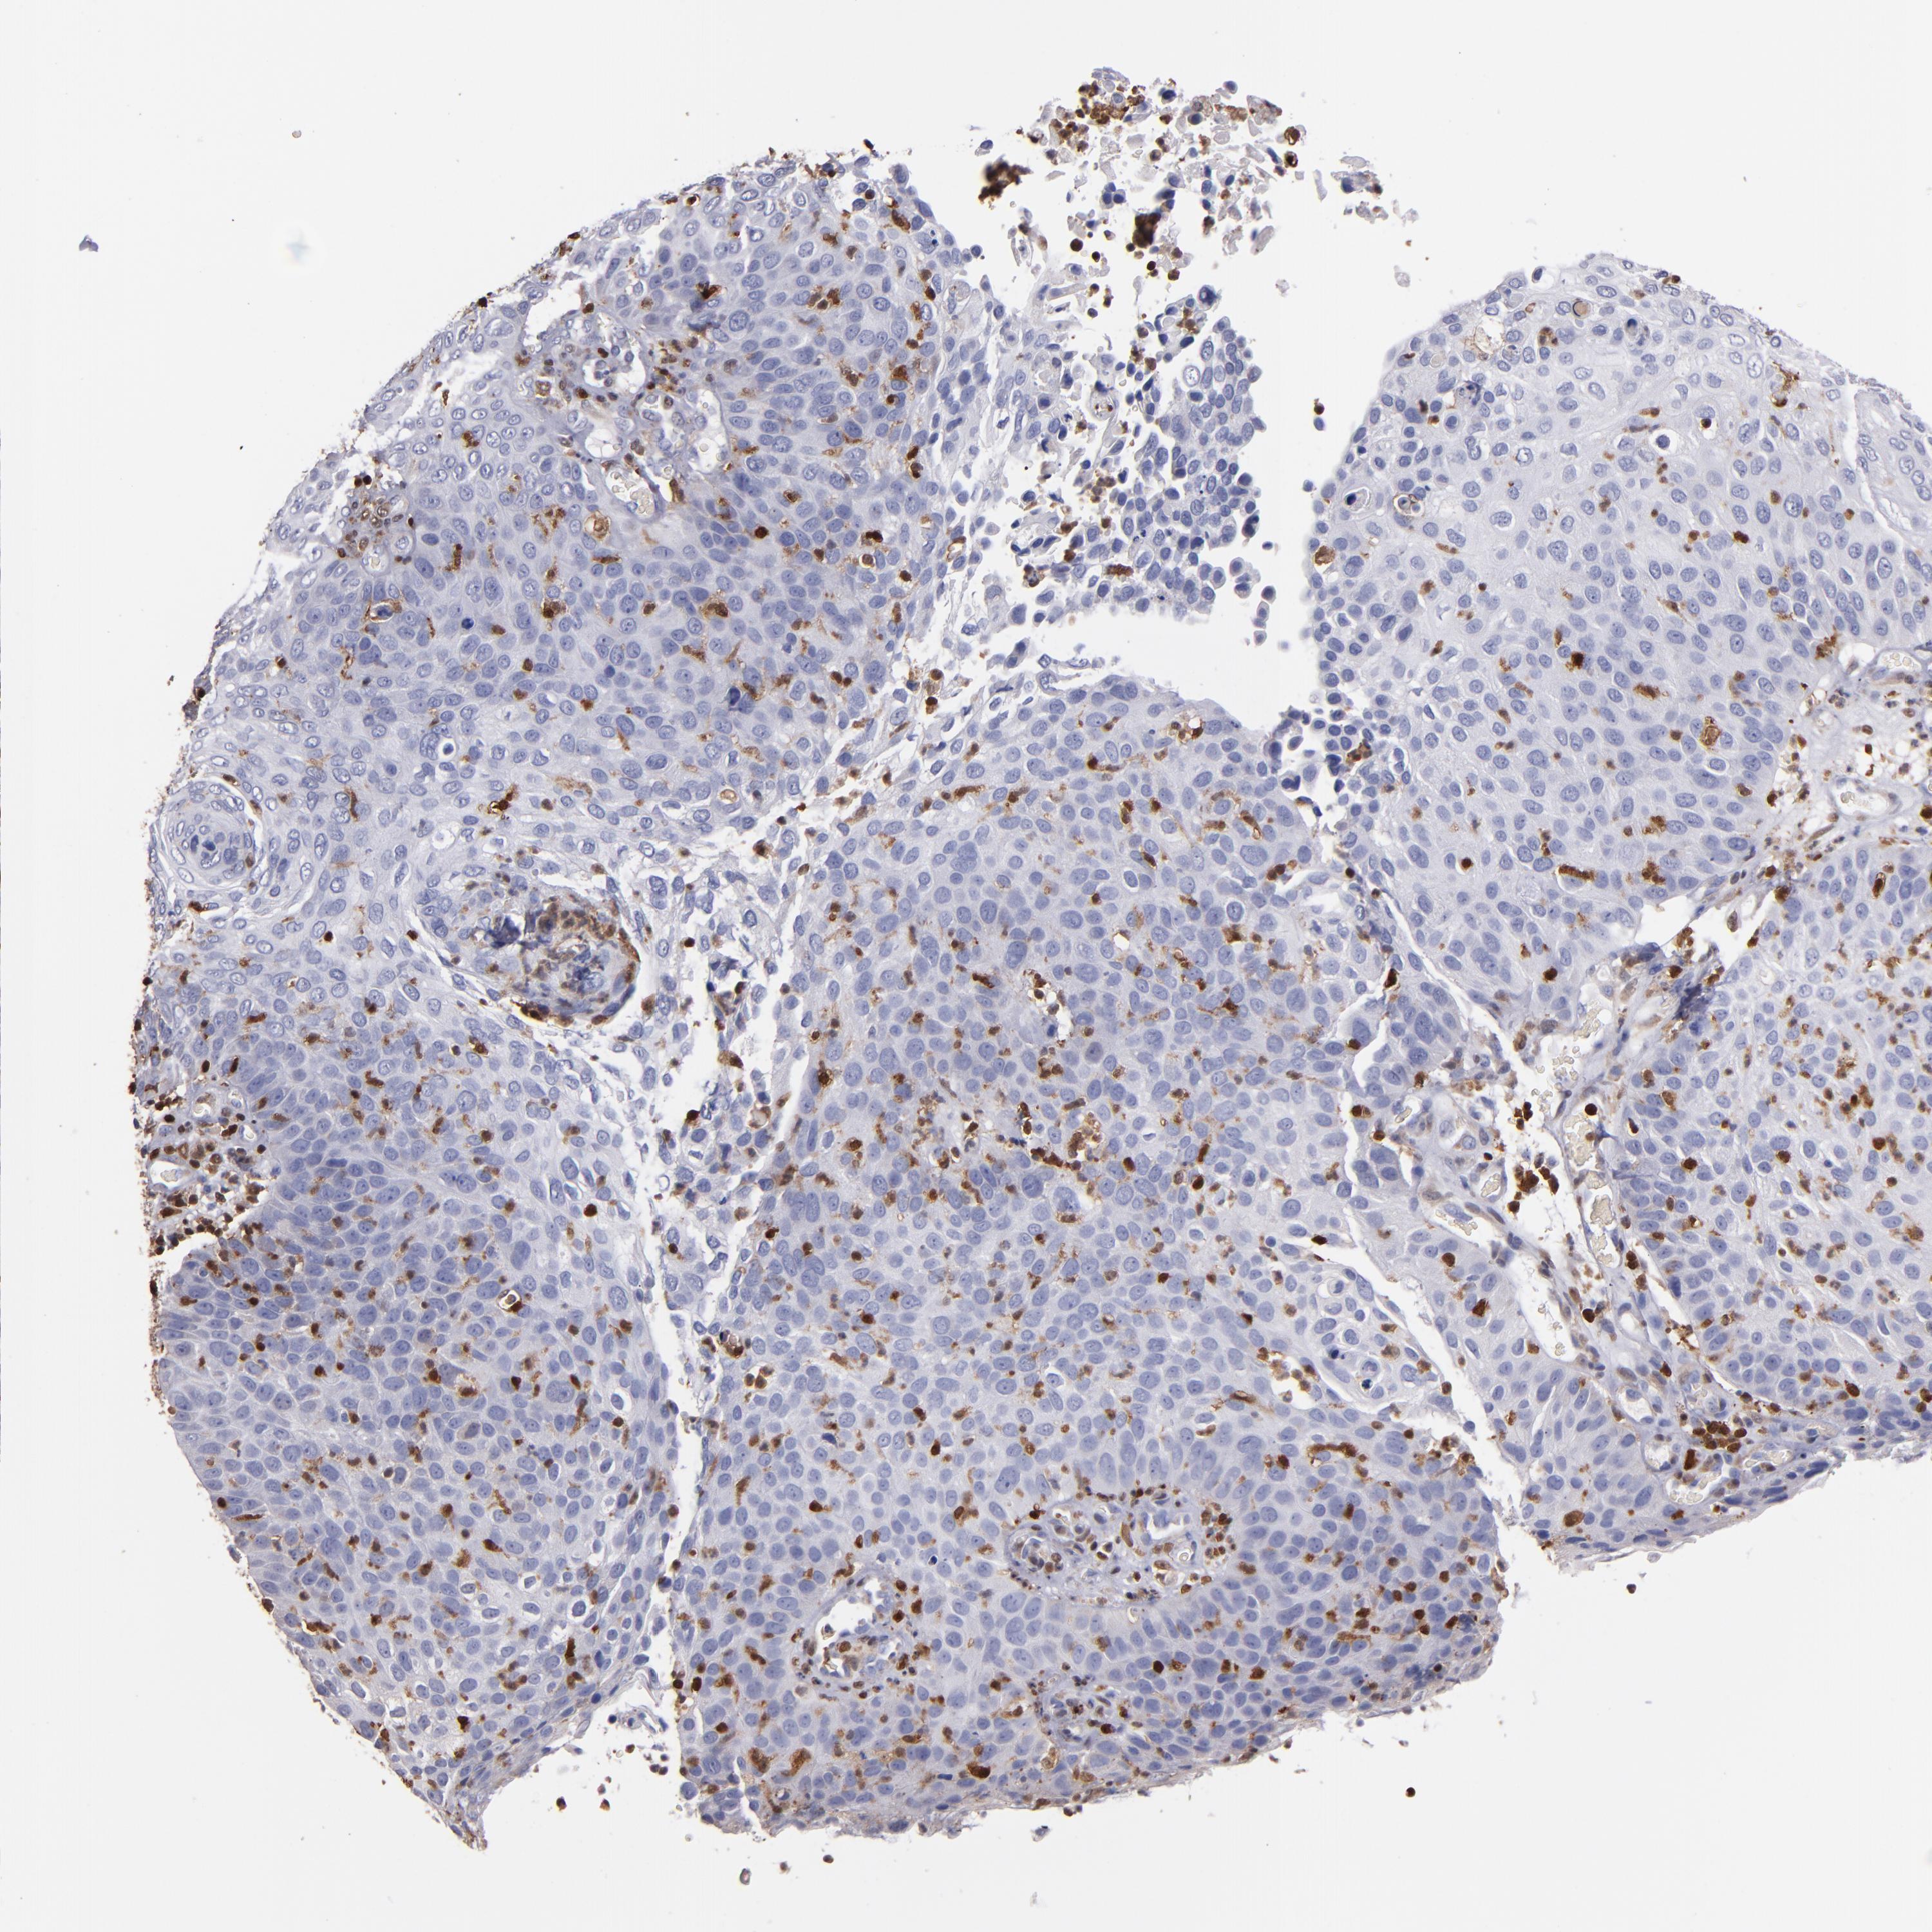

CANCER SKIN CANCER Show tissue menu

Basal cell and squamous cell cancer

SKIN CANCER - Protein expressioni

A mouse-over function shows sample information and annotation data. Click on an image to view it in a full screen mode. Samples can be filtered based on level of antibody staining by selecting one or several of the following categories: high, medium, low and not detected. The assay and annotation is described here.

Each image is clickable and will lead to virtual microscopy that enables deeper exploration of all samples and also displays staining intensity scores, fraction scores and subcellular localization as well as patient and tissue information for each sample.

HPA007973

CAB002618

CAB027387

CAB058698

CAB068227

CAB068228

Basal cell carcinoma

Squamous cell carcinoma, NOS

Squamous cell carcinoma, metastatic, NOS